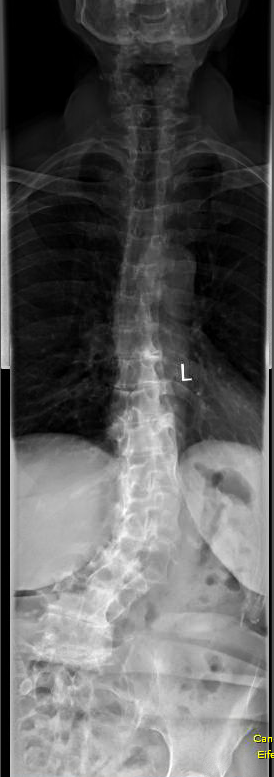

Nur mal so als Beispiel. Das Bild zeigt eine Skoliose mit nur 43°. Die Dame konnte vor Schmerzen aber kaum noch stehen. Der schnelle Verschleiß hat sich aufgrund einer tiefliegenden Skoliose entwickelt, obwohl die noch nicht bei 50° war.